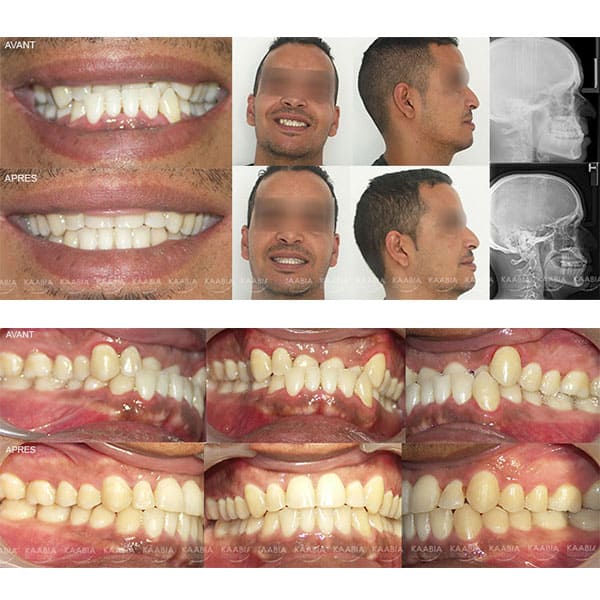

Traitement des retroalvéolies supérieures

Traitement sans extraction